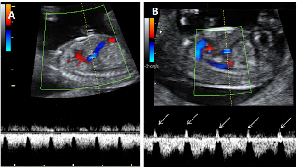

Ecografía del flujo patológico de un feto de la semana 12